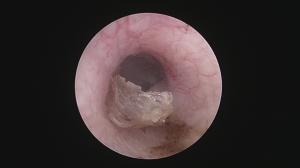

処置後40日後・・

鼓膜が綺麗に再生しています!(手前に見えるのは耳垢のカサブタ状のものです)

耳漏も消失し、快適になっている様子。